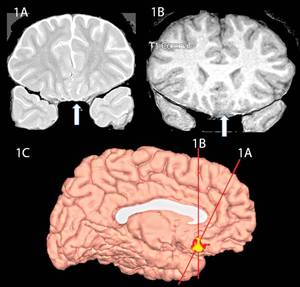

©BMC Neurology 2011;11:151 [doi:10.1186/1471-2377-11-151]

Although damage to the ventromedial prefrontal cortex (vmPFC) is known to affect motivation, a case of a 14-year-old boy with a congenital malformation of the region showed that it can appear as more of a temperamental issue than an acquired amotivational state. The arrows in 1A and B point to the lesion site in the vmPFC (highlighted in the medial left hemisphere surface in 1C), showing hyperintense white matter next to the gyrus rectus and cortical thickening of the left gyrus rectus relative to the right.